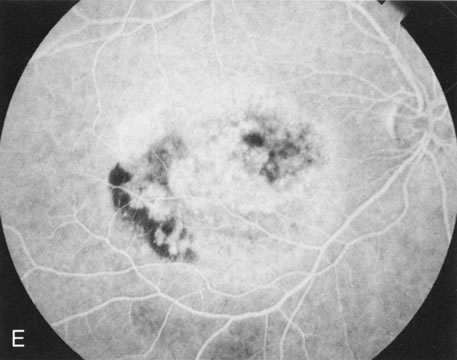

Gyrate Atrophy

Unlike choroideremia, gyrate atrophy funduscopically has well-demarcated scalloped areas of choroidal atrophy. A hyperpigmented border separates the normal and abnormal tissue. These lesions begin as isolated areas in the midperiphery, which then merge to form a garland wreath, with progression peripherally and centrally, sparing only the macula.

FA demonstrates the sharp demarcation between normal and abnormal tissue, the former showing normal background fluorescence, the latter atrophy of the choriocapillaris (Fig. 5). Thus, the normal choriocapillaris background fluorescence in the early stages of gyrate atrophy is in contradistinction to the diffuse choriocapillaris atrophy in the early stages of choroideremia.